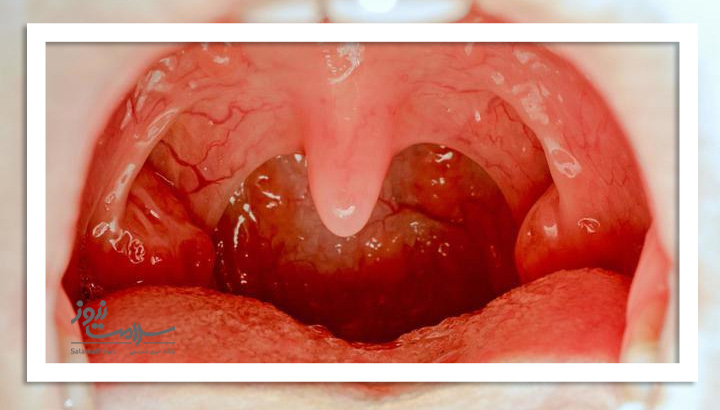

عکس لوزه سالم و ناسالم